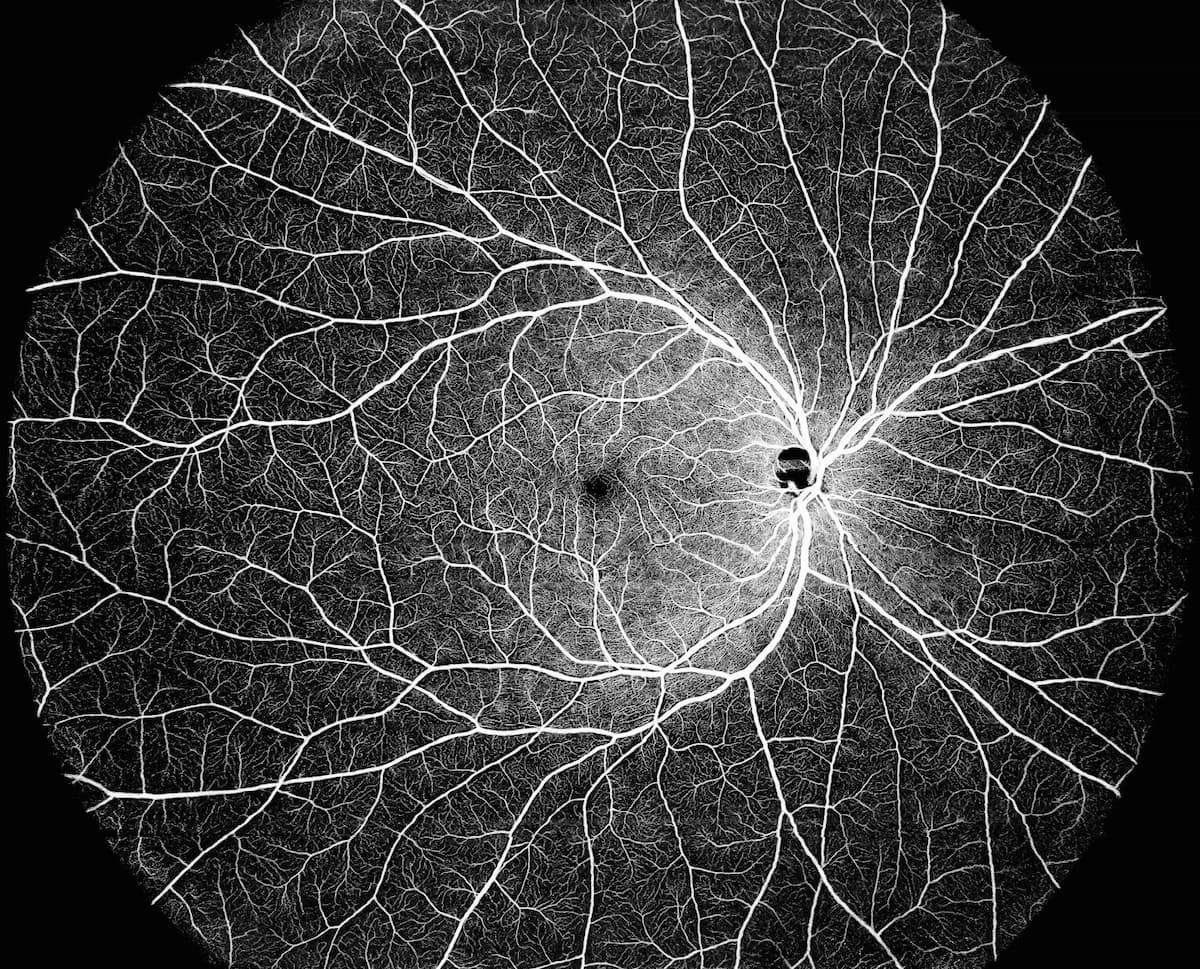

MonacoPro, the next evolution of Monaco from Optos, retains the powerful ultra-widefield SLO and spectral domain imaging while adding additional key product features.

Michael Chaglasian, OD, details results from a study that assessed the new Monaco OCT's efficacy in glaucoma detection alongside ultra wideview imaging.